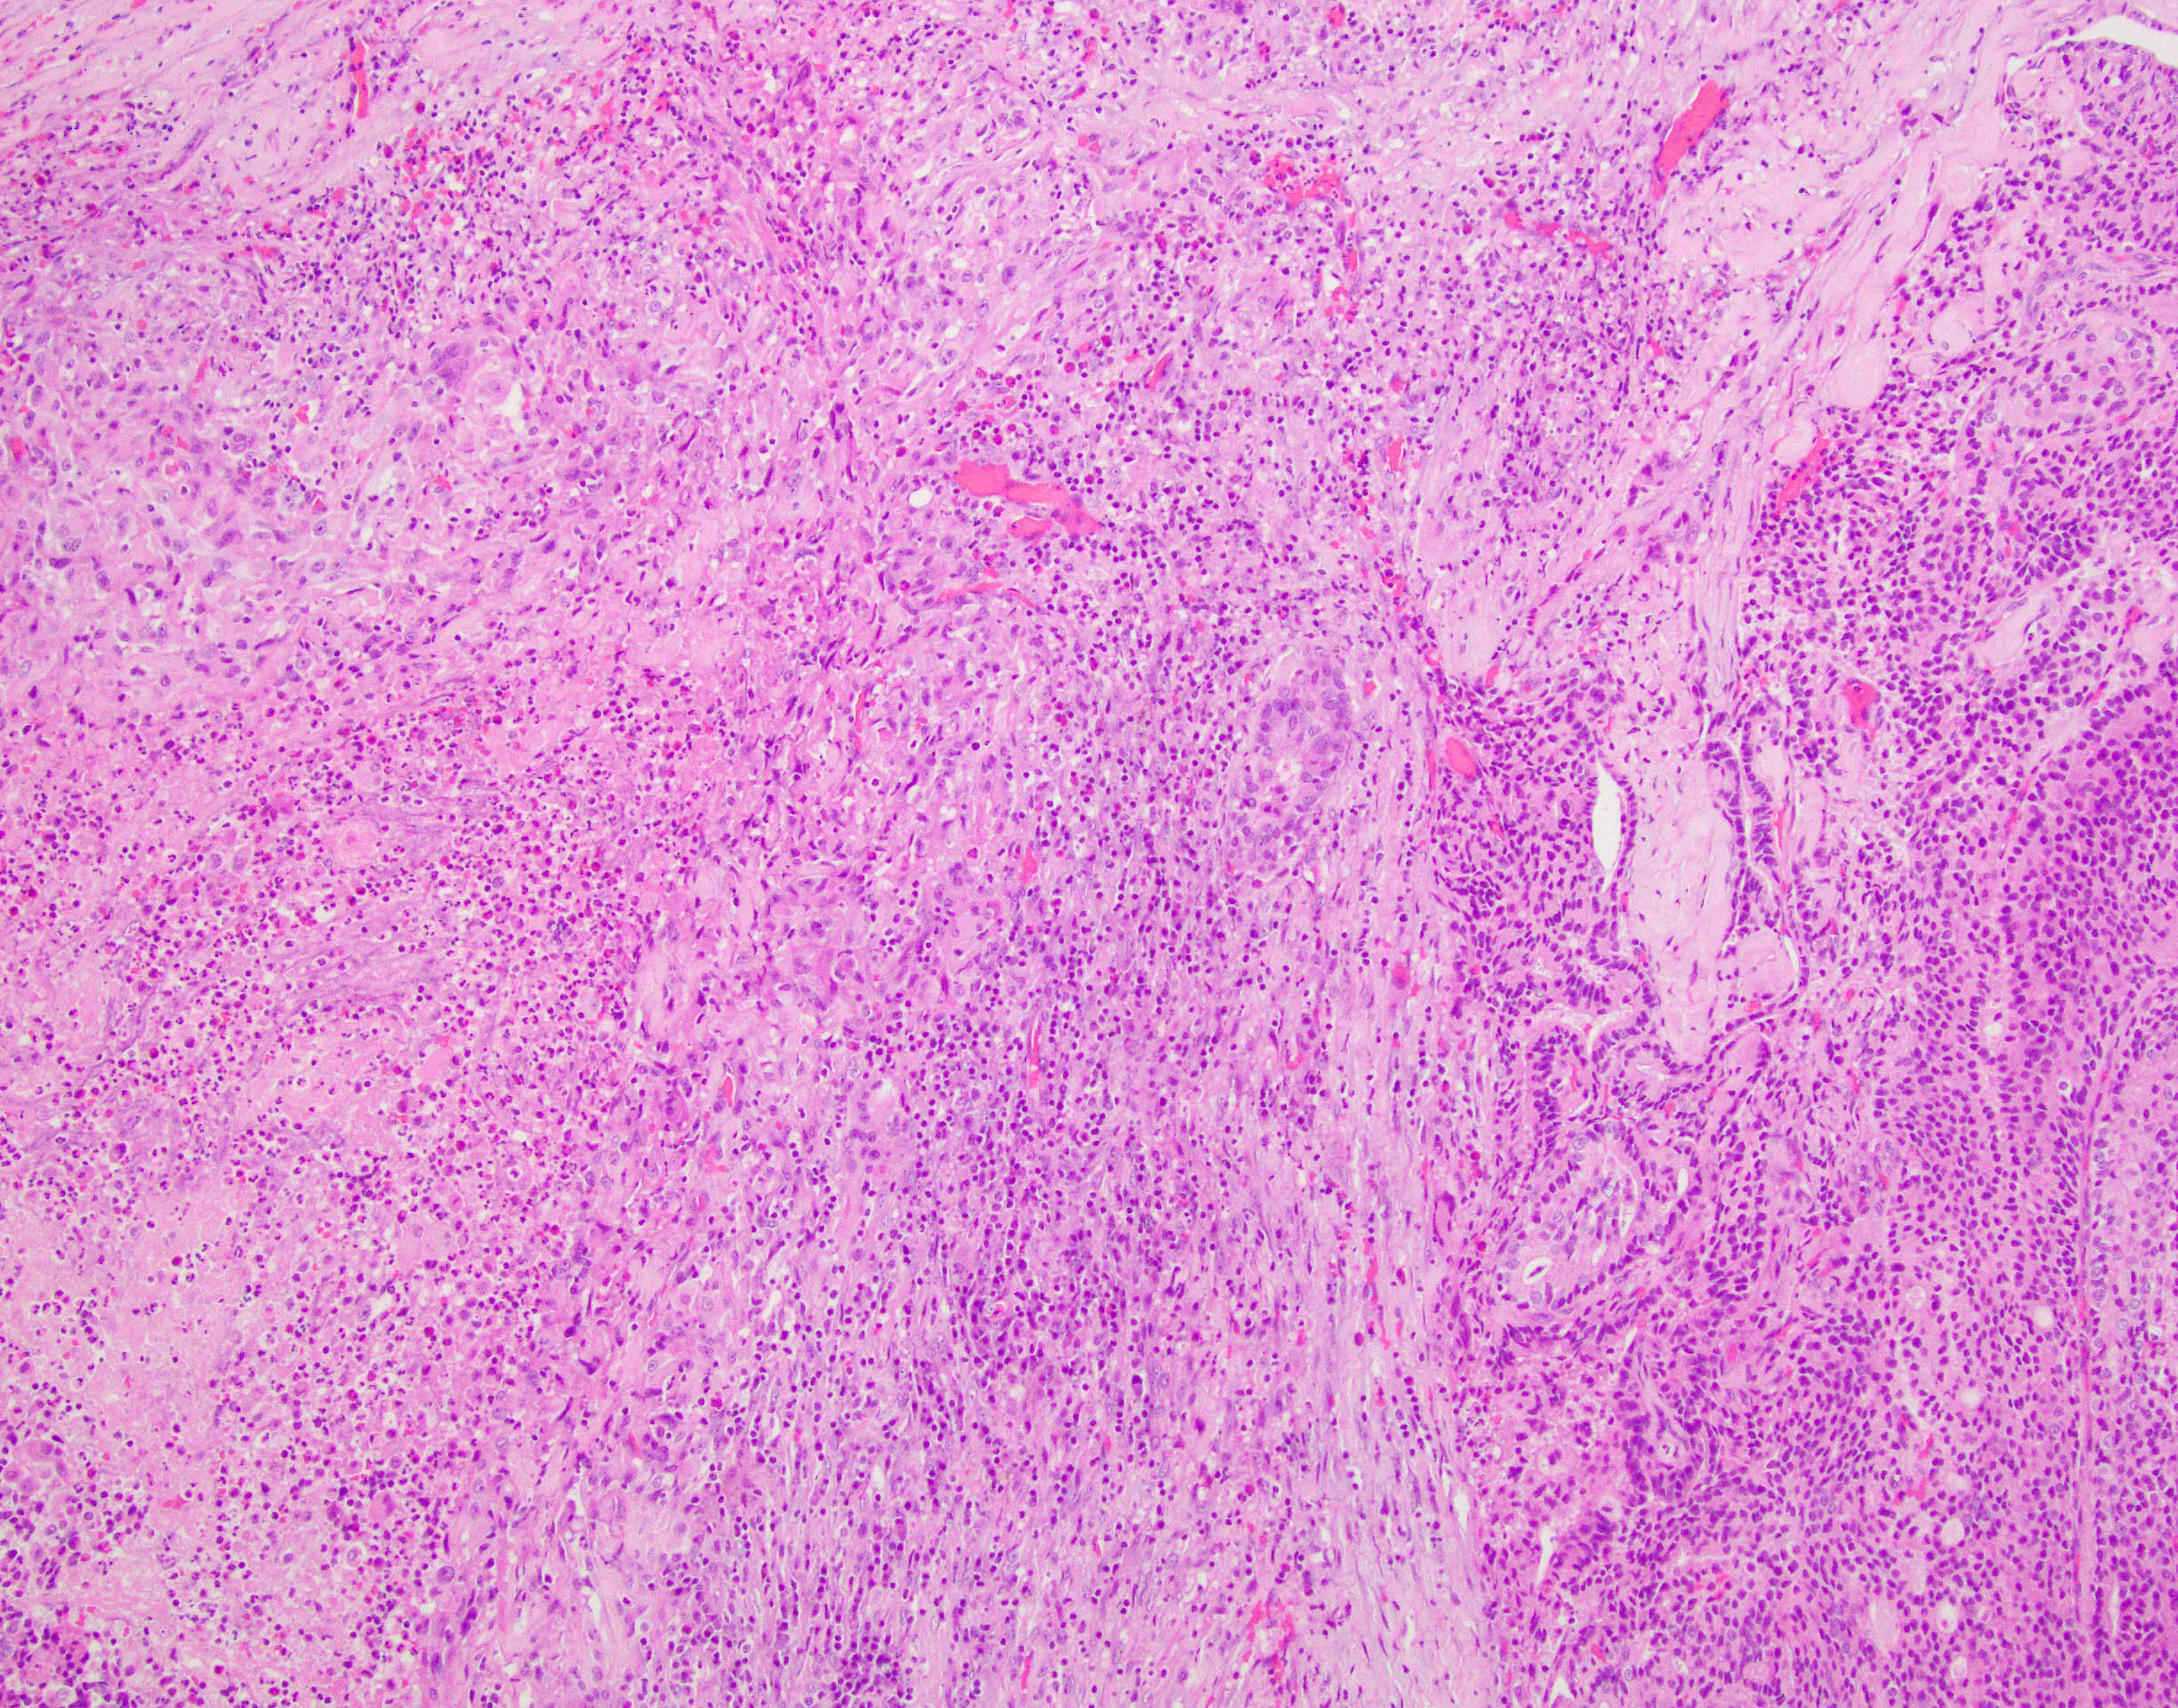

Case history: 17-year-old female with large, solid adnexal mass.

What is the diagnosis?

- Germ cell ...